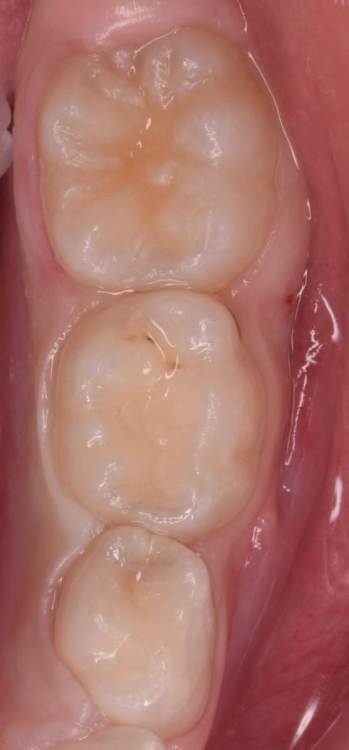

CRAZYDUCK Опубликовано 29 июня, 2022 Автор Поделиться Опубликовано 29 июня, 2022 Герметизация тоже в изоляции . по случаю - герметизация 3.6 лечение кариеса 74 ,75 . 3 1 Ссылка на комментарий